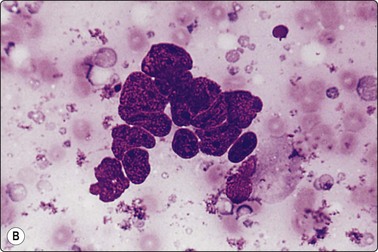

image image

Fig. 5.5 Reactive lymphadenopathy, follicular

Smear derived from reactive follicle. Centroblasts, centrocytes, small lymphocytes and tingible body macrophages with nuclear fragments (A, MGG; B, Pap; HP).